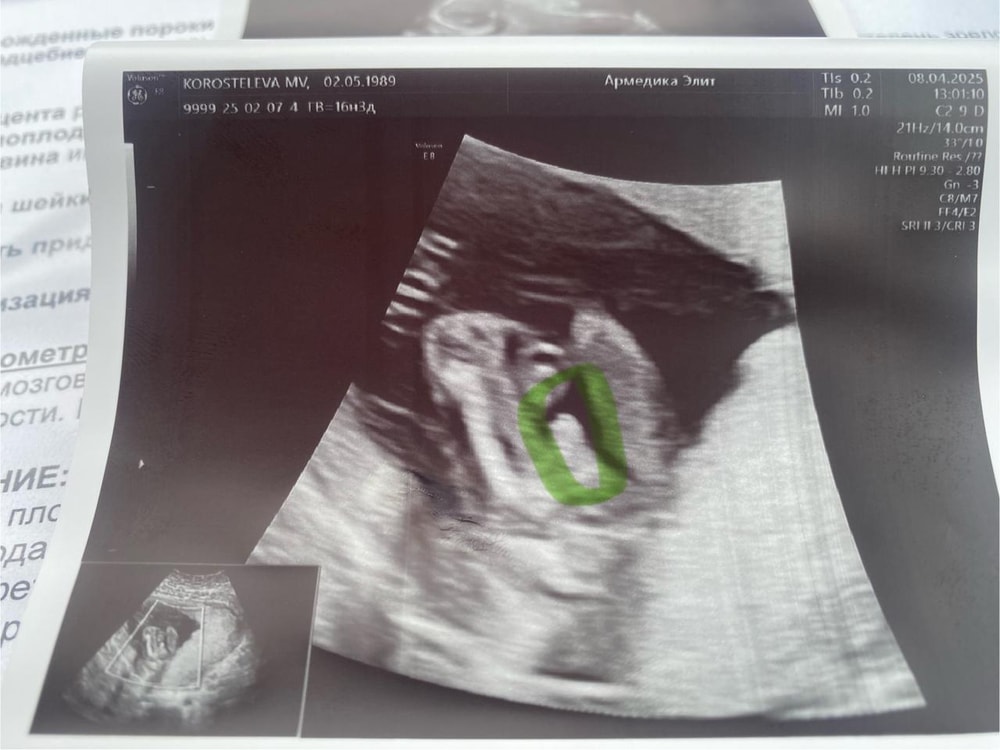

По узи в 16 недель сказали 100% пацан

Виктория, вот мой пацан) даже сомнений никаких не было,что могли с полом ошибиться. 16 недель на снимке

Мошонка и пенис вроде да. У моего старшего тоже хозяйство хорошее все сразу видно было )